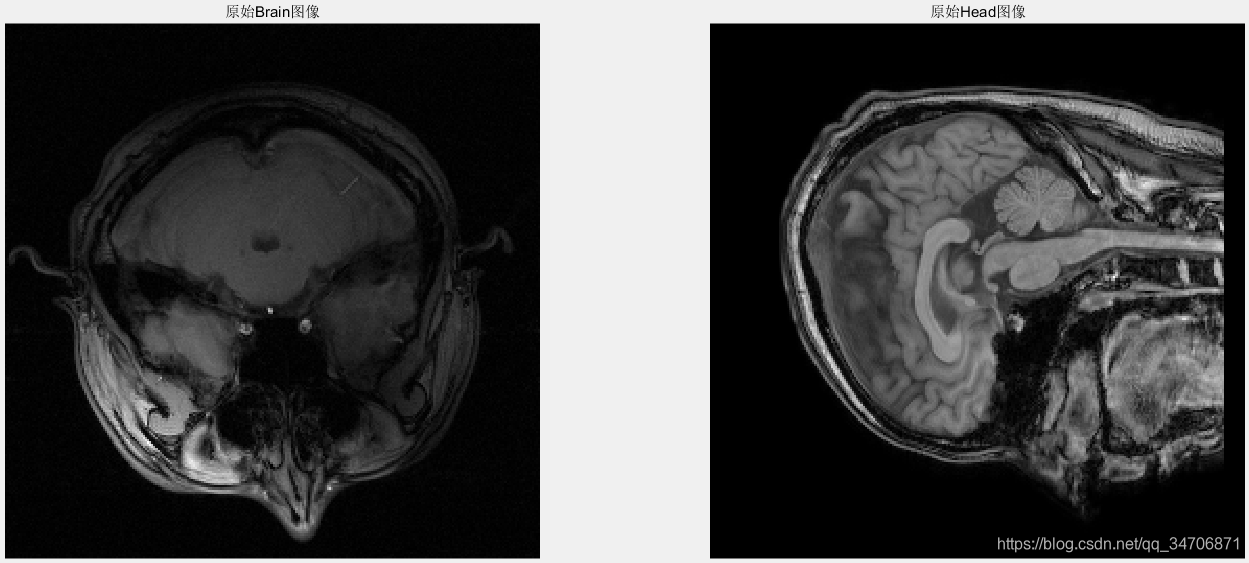

我们主要关注的是第三个方法,欠采样——>再重建。由欠采样图像去重建一幅全采样图像(真实图像),显然是一个NP难的问题(很多全采样图像能对应同一幅欠采样图像)。由于欠采样违反了奈奎斯特采样定理,直接进行频域零填充的时域图像上会发生混叠伪影,如图1、2、3所示。